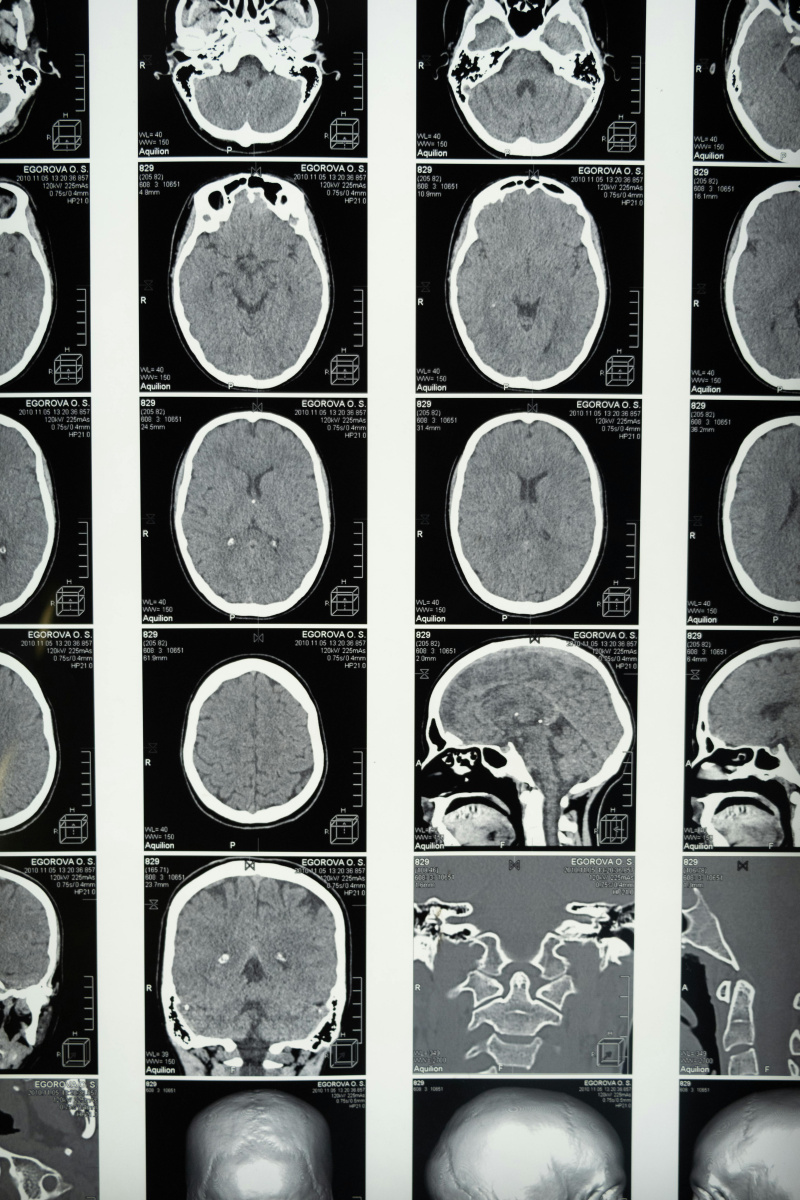

Spesso, nel senso comune, le neuroscienze appaiono come la frontiera del riduzionismo: scopriamo i meccanismi del cervello, si pensa, e scopriremo le fondamenta dell'umano, che a quei meccanismi neurali possono tutti quanti essere ricondotti – come molti auspicavano sarebbe stato per il DSM-5 del 2015 – l'ultima edizione del Manuale diagnostico e statistico dei disturbi mentali –, ovvero realizzare una mappatura dei cosiddetti disturbi mentali in relazione al loro fondamento neurobiologico – tentativo fallimentare, ma che testimonia di una tendenza persistente e centrale della nostra cultura e della nostra contemporaneità. Ma le neuroscienze non sono il braccio armato del riduzionismo: al contrario, possono mostrare come sia illegittima qualsiasi riduzione organicistica dell'umano, e qualsiasi riduzione della mente al cervello.

La stessa razionalità non può essere davvero compresa senza incrociarla con la dimensione dell'intersoggettività, diversamente da quanto ha fatto gran parte della tradizione del pensiero occidentale. Per questa tradizione, per questo canone, l'umano è cogito, teoresi di una realtà che sta là fuori, e che conosciamo attraverso degli a priori. In questa tradizione, a mancare è il corpo. La stessa intersoggettività viene prevalentemente compresa in termini teoretici, ovvero possiamo capire gli altri grazie a una teoria della mente, negli stessi termini in cui possiamo elaborare un problema matematico. Nel paradigma teoretico-“oculocentrico” (nel senso della primato della theorìa, dell'eìdos, della conoscenza come visione), non c'è il corpo e non c'è il movimento: la cognizione è altra cosa rispetto al movimento. È così anche nel modello a sandwich del cognitivismo classico, dove azione, percezione e cognizione sono elementi isolati, e messi in relazione da un flusso di informazioni sulla cui base costruiamo una rappresentazione del mondo: in questa prospettiva, il movimento arriva alla fine, informato e causato dall'elaborazione del pensiero. Questa prospettiva non considera affatto come invece la relazione, che accade tra corpi, sia fatta di movimento: “è un andare verso o un allontanarsi da; è cercare quello che ci manca, è un proiettarsi verso l’altro da sé, ma proiettarsi non solo in senso metaforico bensì in senso fisico, in senso corporeo. Tant’è vero che, per mantenersi biologicamente in vita, per noi umani è centrale non solo l’omeostasi, cioè la capacità di movimento e scambio tra interno ed esterno, ma anche l’allostasi, la reciproca regolazione tra sé e altro da sé”. Azione e percezione, lungi dall'essere elementi isolati e distinti, “sono due facce della stessa medaglia e sono l’ingrediente essenziale di ciò che chiamiamo cognizione”. Tutto, insomma, nasce dal movimento: “sappiamo con sempre maggiore evidenza che le cosiddette parti motorie del cervello sono parte integrante degli apparati che ci permettono di riconoscere quello che c’è attorno a noi, dagli oggetti inanimati, al modo in cui mappiamo lo spazio, al senso che diamo alle azioni e alle esperienze altrui”. La percezione e l'azione non stanno in successione, ma si danno insieme: il sistema motorio non è un “organo esecutivo”, laddove lo scopo di un movimento viene mappato da qualche altra area del cervello, ma è il sistema motorio stesso che mappa le azioni, ovvero è caratterizzato in termini di scopo. La neuroscienza, qui, pensa insieme a Merleau-Ponty quando parlava di practognosia, ovvero una conoscenza determinata dalle potenzialità del corpo.

È nello spazio noicentrico, come si diceva, che prende corpo la nostra esperienza. Si tratta di mettere al centro il corpo che si muove in uno spazio – ciò che è stato ben compreso con la scoperta dei neuroni specchio, che, essendo la base fisiologica del meccanismo di risonanza motoria, ci permettono di connetterci all'altro a livello pre-intenzionale e pre-linguistico. Neuroni specchio che, vale la pena di ricordarlo, esistono in molte specie animali, ma che nell'animale umano si applicano non solo nelle azioni dotate di finalità, ma in tutti i movimenti: per questo, scrivono Gallese e Morelli, “noi siamo la vera specie mimetica”, perché possiamo parlare di imitazione quando si riproducono sia lo scopo delle azioni altrui sia i movimenti per arrivare a quello scopo. Riflettere sull'empatia in quanto sentire con l'altro – legata all'attività dei neuroni specchio – ci conduce a uscire dal recinto del riduzionismo: noi siamo costantemente nella relazione, siamo costantemente presi in un processo di riflessione dell'altro nel sé e del sé nell'altro, senza che questo cancelli la distinzione tra sé e altro (l'altro è sempre un “come se”: vi accediamo solo grazie al modello della simulazione incarnata), ma che li rende concepibili unicamente entro un processo: un processo in cui ciò che emerge non è riconducibile, riducibile, alle proprietà costitutive, e che, ancor prima, è dove sia l'io che l'altro sono a loro volta costituiti e prendono forma. Il rispecchiamento negli altri è sempre un riconoscere e un riconoscerci: “siamo quello che riconosciamo di noi attraverso la nostra auto-percezione combinata con l’etero-percezione, in un tempo e in un contesto”.